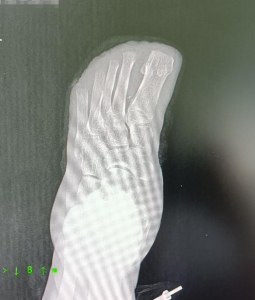

三周后,成功诱导下肢微血管网再生,恢复血运,避免了足部进一步坏死,保肢成功。

术后足部成功测出体温

目前,陈大叔已经出院,能自己步行。